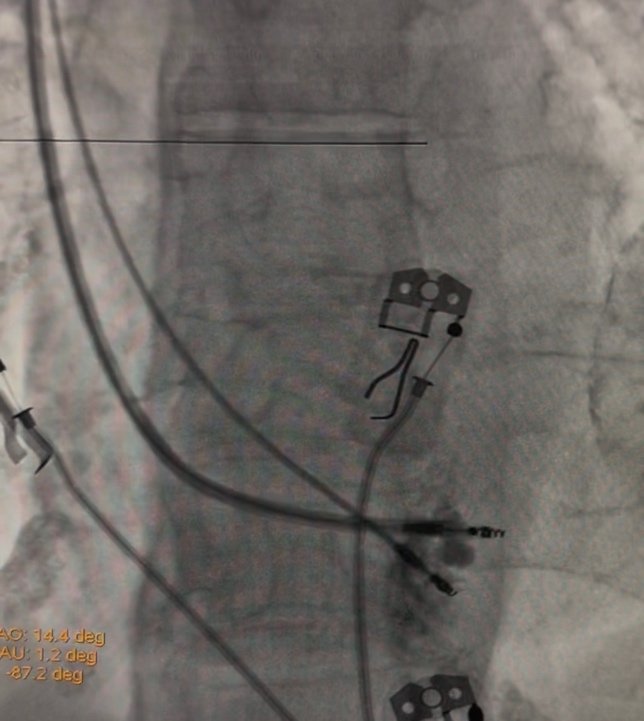

La forma más común de realizar este cierre es mediante un procedimiento mínimamente invasivo:

Se realiza bajo anestesia general.

Se hace una pequeña punción (similar a un cateterismo) en una vena de la ingle (pierna).

Se introduce un catéter a través de la vena hasta llegar al corazón y la Orejuela Izquierda. A través del catéter, se despliega un dispositivo de cierre (que parece un pequeño paraguas o tapón) dentro de la Orejuela. Este dispositivo sella permanentemente la abertura de la Orejuela.